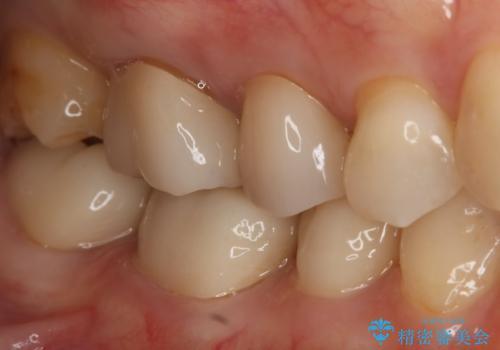

- 右上7番の銀歯のやりかえを主訴に来院された患者様です。

切削量・形態を考慮し、セラミックインレーでの治療を計画しました。

インレー治療では自分の歯を多く残すことが出来ます。